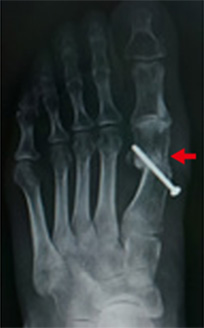

手術については、第一中足骨の骨切り術というのが一般的です。切る場所によって大別すると近位骨切り術、骨幹部骨切り術、遠位骨切り術に分かれます。

術式は200種類とも言われ、一部のみ紹介します。図は母趾と示趾に対して、近位骨切りを行った場合についての変化です。

最終的には切っただけではだめで、術中に母趾を螺子またはプレートで固定します。

手術画像:日本足の外科学会